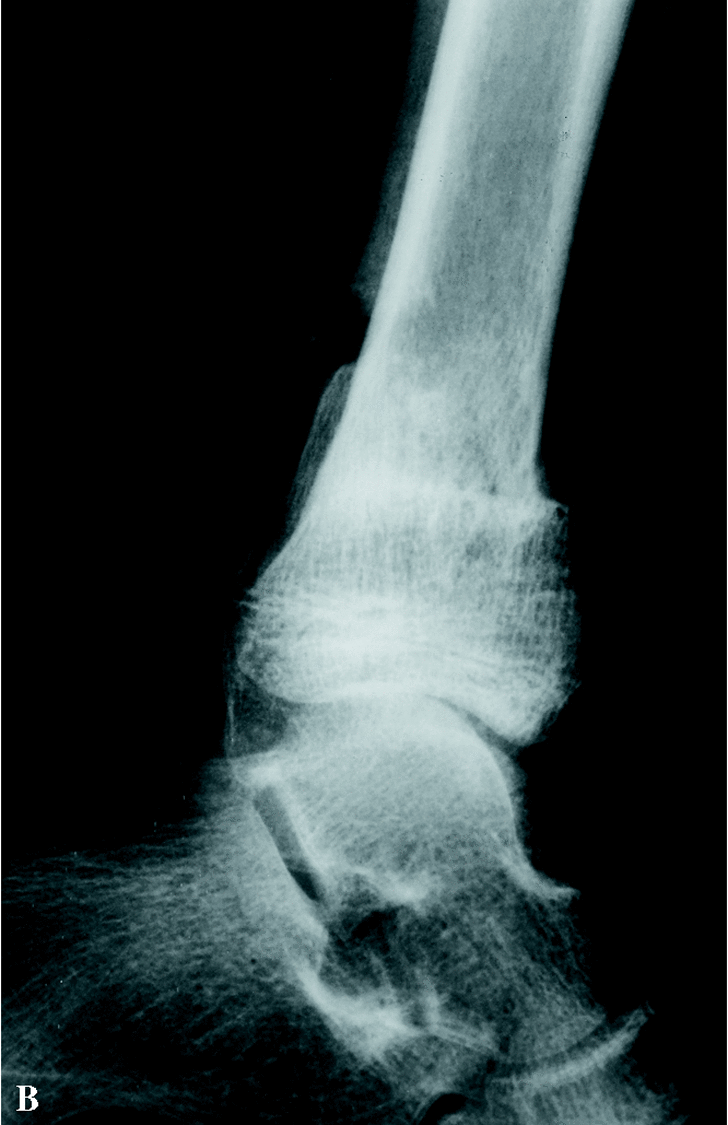

Paciente varón de 13 años que acude por primera vez a nuestras consultas con el diagnóstico previo de pseudoartrosis congénita de peroné con deformidad en valgo de tobillo derecho, sin una neurofibromatosis asociada. A los 16 meses de edad acudió al traumatólogo por tumoración en cara externa de tobillo derecho clínicamente asintomática. Tras realizar un estudio radiológico se diagnosticó de pseudoartrosis congénita de peroné (Fig. 1). Fue intervenido quirúrgicamente resecándose el foco de pseudoartrosis, sin aporte de injerto. A los 11 años, fue nuevamente valorado por presentar importante valgo de tobillo derecho; en la radiografía simple se apreció persistencia de pseudoartrosis peronea. Durante la cirugía se realizó una limpieza del tejido fibroso de la pseudoartrosis, añadiendo en esta ocasión injerto óseo de cresta iliaca, realizándose también una epifisiodesis medial de la tibia con tornillo AO (Fig. 2). Se inmovilizó con yeso. No mejora tras la cirugía.

Cuando acudió a nuestras consultas presentaba un valgo de tobillo derecho y una discreta cojera por dismetría de miembros inferiores (el miembro inferior derecho es 19 mm más corto). Clínicamente estaba asintomático. En la radiografía simple se observó un valgo de la articulación tibio-peroneo-astragalina de 18°, así como la pseudoartrosis del peroné (Fig. 2). Se decidió intervenir quirúrgicamente, mediante técnica de Langenskiöld, tras retirada del tornillo del maleolo medial: se resecó el tejido fibroso y se refrescó el extremo proximal; se realizó una osteotomía en el tercio inferior de la tibia, con extracción de una cuña interna para lograr un efecto de varización, sintetizándola con tres agujas de Kirschner introducidas desde el maleolo interno y, por último, se procedió a cruentar la cara externa de la metáfisis distal tibial y la cara interna de la metáfisis distal del peroné con aporte de injerto óseo. Se inmovilizó con férula de yeso. En el mismo acto quirúrgico se realizó epifisiodesis proximal percutánea de la tibia izquierda, para igualar la longitud de ambos miembros, dado que a la dismetría existente se añadía la cuña extraída de tibia derecha. A las seis semanas, tras observar en las radiografías formación de callo, se retiraron las agujas y se inició la carga. Tres meses tras la cirugía se apreció la consolidación radiológica tibio-peronea, con alineación correcta del tobillo (Fig. 3), clínicamente sin síntomas y con una movilidad normal.